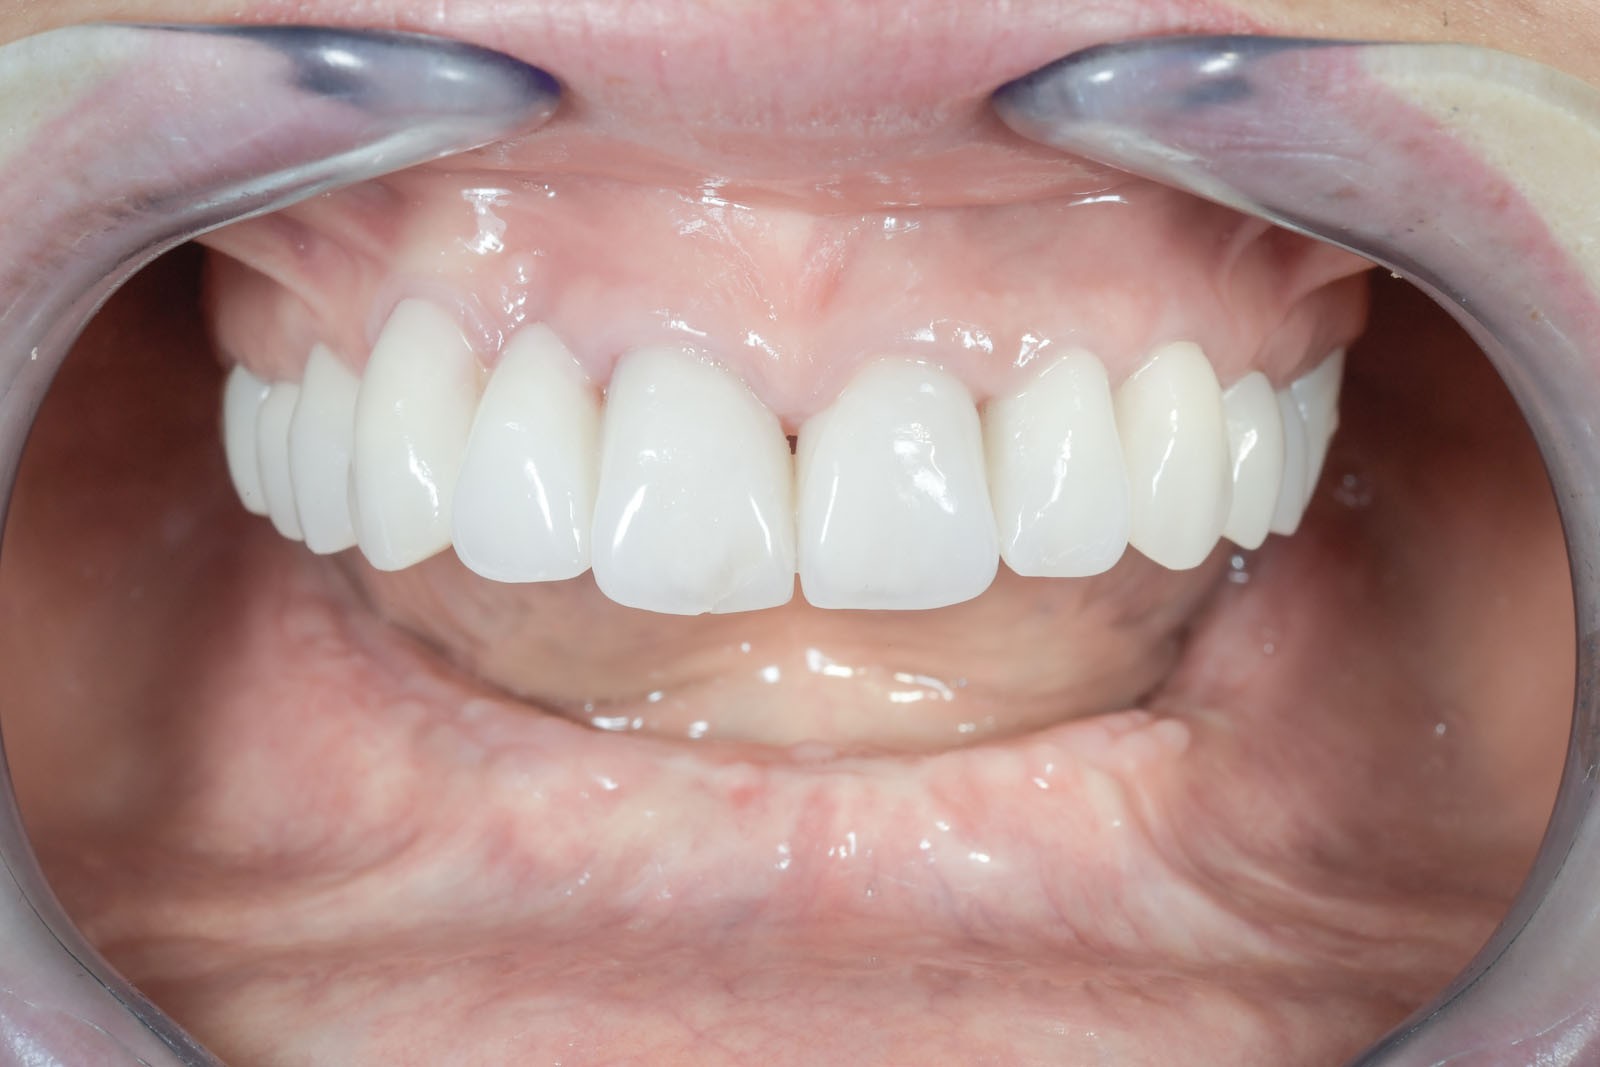

Przy bezzębiu zawsze istnieje możliwość wykonania uzupełnień protetycznych bez zastosowania implantów i są to całkowite protezy osiadające. W zależności od stanu kości szczęk i żuchwy można wykonać protezy lub mosty mocowane na implantach. Mocowanie protez na implantach może być rozłączne, jak w przypadku protez Overdenture, zwanych również nakładowymi. Oznacza to, że proteza w każdej chwili może być odczepiona od platform implantów przez pacjenta i wyjęta z jamy ustnej. Najbardziej jednak pożądane przez pacjentów rozwiązania protetyczne przy bezzębiu to stabilne, niezdejmowalne mosty, które cementuje się lub przykręca na stałe do implantów. One najlepiej imitują estetykę i funkcję naturalnego uzębienia.

Jest to opatentowana metoda rekonstrukcji implanto-protetycznej kompletnego uzębienia stosowana przy bezzębiu zarówno dla dolnego, jak i górnego łuku zębowego. Bazuje na charakterystycznie wszczepionych 4 implantach zębowych, stąd nazwa Wszystko na 4. Dwa środkowe wprowadzane są w kość prostopadle do jej brzegu i równolegle do siebie, dwa boczne wszczepiane są pod kątem 45 stopni. Rozwiązanie protetyczne to most przykręcany na stałe do implantów, który może być zakładany natychmiast po zabiegu implantacji lub w czasie odroczonym. Gwarancją natychmiastowego przywrócenia funkcji żucia jest odpowiednia siła osadzania implantów mierzona dynamometrycznie w trakcie ich wszczepiania oraz należyta staranność wykonania i osadzenia prac protetycznych.